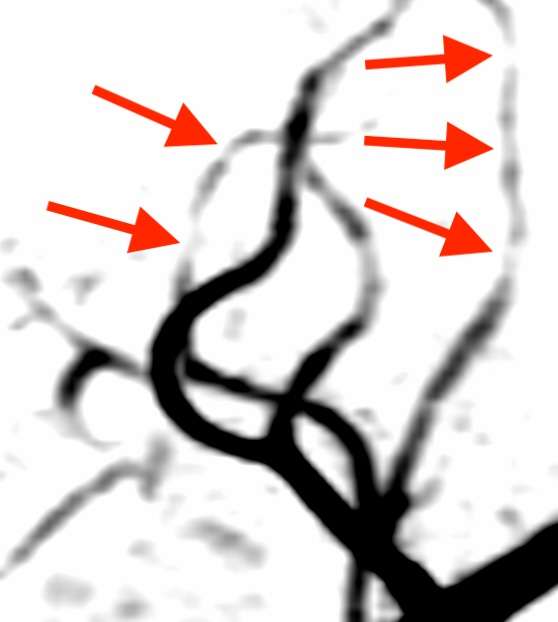

後大脳動脈(後頭部から上へ向かう血管)という血管が、所々細くなっています。

中大脳動脈(側頭部から頭頂部へ向かう血管)にも、同様の所見が見られました。

こうした画像所見から、可逆性脳血管攣縮症候群(RCVS)と診断しました。RCVSでは、様々な場所の脳血管が縮んで細くなる多発性分節性狭窄1)という特徴があり、進行とともに血管の先端部から中心部に攣縮が移動する求心性移行2)という経過をとる事などから、頭痛の場所が移動する事があります。